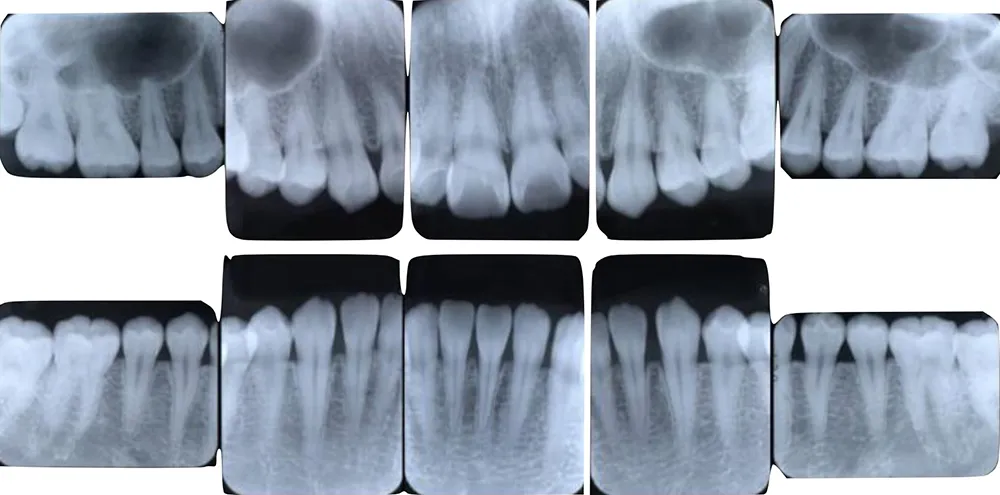

視覚資料として提出する検査結果の一例

レントゲン写真